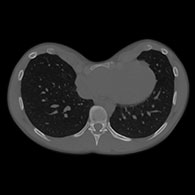

Indice di Haller

L'indice di Haller è stato istituito nel 1987 per valutare l'importanza di un Pectus sulla base di un calcolo effettuato su un'immagine digitale.

Viene stabilito tramite TAC nel punto più profondo della depressione: è il rapporto tra la larghezza e la profondità massima.

L'indice di Haller permette di misurare con maggiore precisione la profondità del petto escavato specialmente nelle donne, nelle quali la deformazione è difficile da valutare a causa del volume mammario. Quanto più l'indice di Haller è alto tanto più il Pectus Excavatum è profondo.

È pratico e ancora utilizzato, ma dà un'idea imperfetta dell'importanza della depressione e non pregiudica in alcun modo un possibile e raro impatto funzionale sul petto.